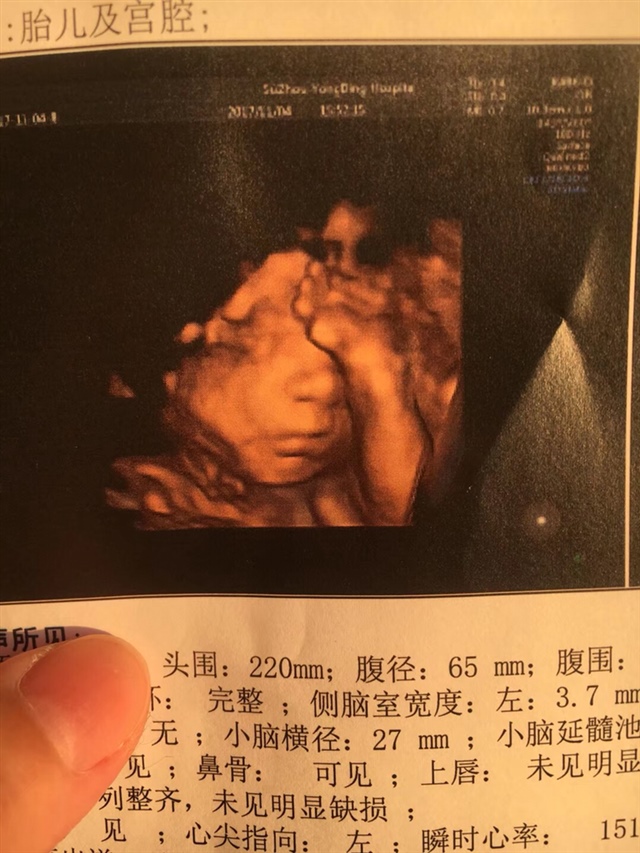

孕26周+1天

从胎心率上来看应该是女孩,我家儿子137,这胎已知女儿147,也看了几张别人的,大概率是女生